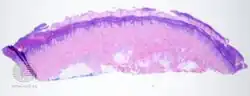

Talon noir-pathology